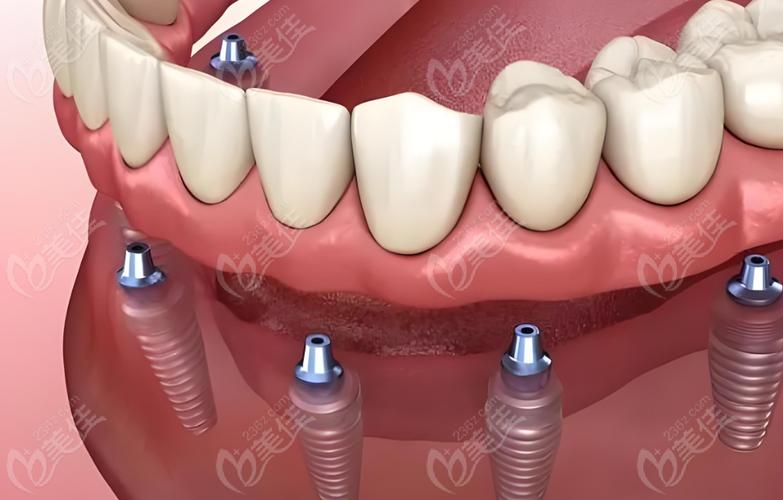

种植牙是一种通过外科手术的方式,将人工材料(通常是纯钛或钛合金)制成的种植体(类似牙根的结构)植入到缺牙部位的牙槽骨内,待种植体与牙槽骨紧密结合(这个过程称为“骨结合”)后,再在种植体上安装基台和牙冠,最终恢复牙齿的形态、功能和美观的修复方式。

主要组成部分

- 种植体: 植入牙槽骨内的“人工牙根”,由生物相容性极佳的纯钛或钛合金制成,它负责替代天然牙根,为上面的修复体提供稳固的基础。

- 基台: 连接种植体和牙冠的中间部件,用于将牙冠的力量传递到种植体上。

- 牙冠: 可见的部分,由全瓷、烤瓷或金属烤瓷等材料制成,模拟天然牙的形态和颜色,行使咀嚼功能。

- 全口牙缺失(可用多颗种植体支持固定桥或覆盖义齿)